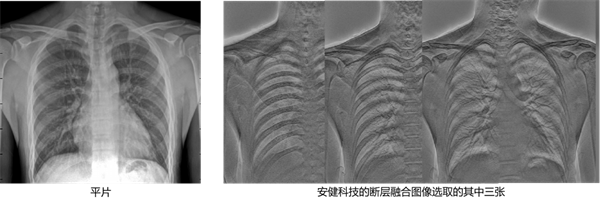

断层融合通过指定截面范围内的单次断层扫描获得容积数据,结合线束CT重建和图像处理技术,提供特定范围内的多层次断层图像,可以清楚地显示病变纵向边缘形态和邻近结构的变化,为进一步研究肺结节边缘的形状、邻近结构的改变、肺门、气管、支气管及其分支的显示提供了新的手段。

它可以显著提高肺结节的检出率和诊断准确性;且具有较高的空间分辨率,图像不受金属伪影的影响,这对于检测细微病变和提高诊断准确性非常有益。此外,辐射剂量相对较低,价格相对较低,极受到临床技师和患者的喜爱。

传统断层融合技术采用球管打角度的方法进行扫描,受限于平板探测器小于43CM的有效探测范围,一次断层融合只能够重建出小于43CM范围的冠状面图像,对于全脊柱、双下肢等大部位断层融合的检查则无法一次扫描重建获得图像。

而今,安健科技最新推出的行业首款1.1米超大断层融合多功能胃肠机采用平行扫描方式,扫描过程中平板探测器和球管平行运动,以此达到了目前立卧双位下的业内最长扫描范围1.1米,弥补了这方面的一些不足。